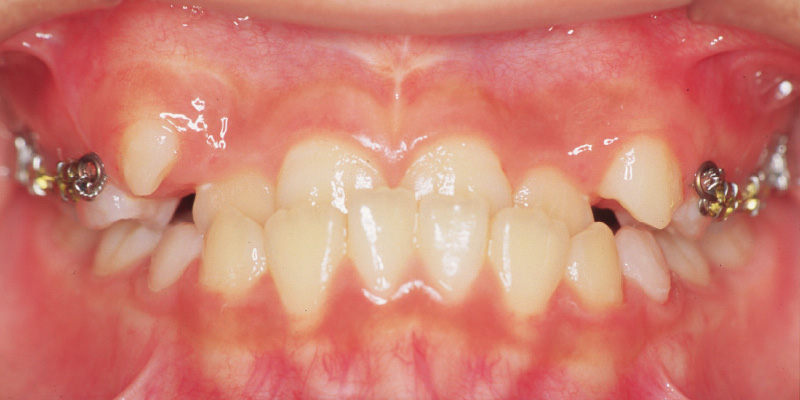

矯正治療後

[16歳1か月/2年9か月の矯正治療後]

【お顔】治療中も下顎の成長は持続し、オトガイの位置も前にしっかりと出て、バランスの良い顔立ちとなっています。【口腔内】上下前歯の前後的なギャップも解消し、安定した歯並びを得ることができました。

小臼歯を抜歯して得たスペースと、下顎の反時計回転の成長メカニクスを用い、成長スパートとの相乗効果を狙ってさらに良い方向に成長しました。

R

L